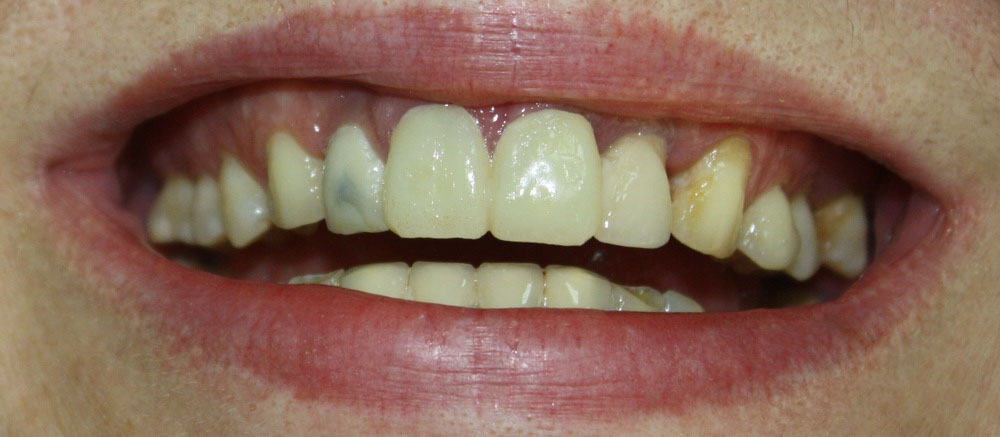

Краткая предыстория: Пациентка, молодая женщина, несколько лет назад потеряла боковой резец. Пока готовилась к протезированию, резко ухудшилось состояние и объемы костной ткани в области отсутствующего зуба. Несколько раз ей делали операцию остеопластики («наращивания костной ткани») с помощью биоматериалов, но безрезультатно — расходились швы, материал нагнаивался или рассасывался. Это продолжалось в течение двух лет.

В совершенном отчаянии она пришла к нам на прием. К этому времени ситуация усугубилась — появилась рецессия десны в области центрального резца, сильно ухудшился внешний вид десны:

Учитывая то, что эти зубки попадают в зону улыбки, мы должны создать максимально эстетическую конструкцию с учетом пожеланий пациентки. Данную задачу мы делим на две части:

Давайте еще раз вернемся к началу:

И посмотрим, что получилось в конце: